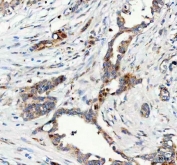

IHC staining of FFPE human pancreatic ductal adenocarcinoma tissue with FOXO3A antibody. HIER: boil tissue sections in pH8 EDTA for 20 min and allow to cool before testing.